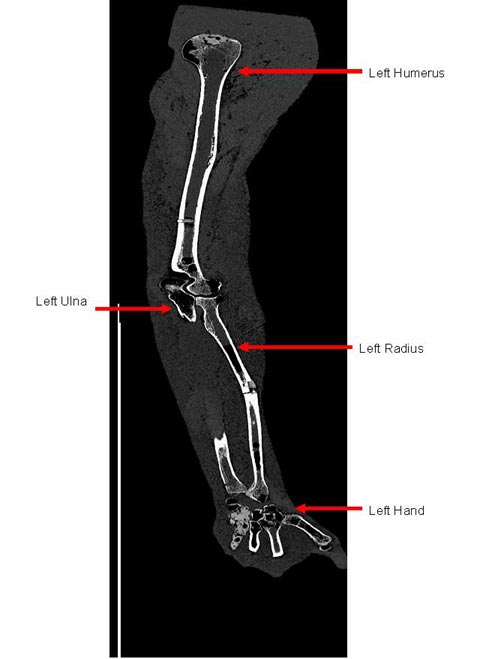

Case 0102 was the first whole body donation to the U.S. Transuranium Registry (in 1979). This case was published in 1985 – in a special issue of the Health Physics journal (Volume 49, Number 4; October 1985) dedicated to the donor. Half of this gentleman’s skeleton, encased in tissue equivalent plastic, still provides a unique anthropomorphic ‘phantom’ for calibrating whole body counting systems at DOE laboratories – and internationally.

In collaboration with the Pacific Northwest National Laboratory’s (PNNL’s) ‘In Vivo’ Monitoring Program, USTUR is now using high-resolution planar germanium detectors to ‘count’ 241Am activity in various parts of donated whole bodies, before tissues and organs are sampled for radiochemical analysis. For each individual case, and also for the Case 0102 ‘real 241Am phantom,’ USTUR aims to develop a three-dimensional mathematical model, or ‘virtual phantom.’ These virtual phantoms will represent the bones of the torso, head and limbs, their radionuclide content, and the overlying thickness of soft tissue. Their availability will allow the counting efficiency of different detector types and configurations to be modeled (calculated accurately) for people of different anatomical build and body size.

Americium-241 is present as a 'contaminant' radionuclide in the majority of USTUR Registrants with accidental plutonium intakes. It emits a 59.5 keV photon which can be detected outside the body (if the activity is high enough). However, at this relatively low photon energy, the amount of self-absorption in body tissues depends rather critically on tissue thickness (body build) and the distribution of the activity within the body.